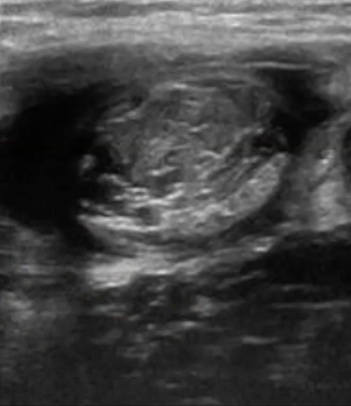

Por aquí vemos una fibrosis del recto anterior, una antigua rotura, no tratada que acabó fibrosando el septo.

Ya no existe septo definido y en su lugar encontramos una masa dura y poco flexible que compromete al recto anterior.

Evitar los procesos cicatriciales aberrantes, es una labor del fisioterapeuta.

Con tu ecógrafo podrás monitorizar la evolución de la lesión y valorar las características de la cicatriz. A través de la elastografía, incluso, podrías saber cómo de rígida es la misma. Y en base a esto, hacer un manejo más conservador o invasivo.